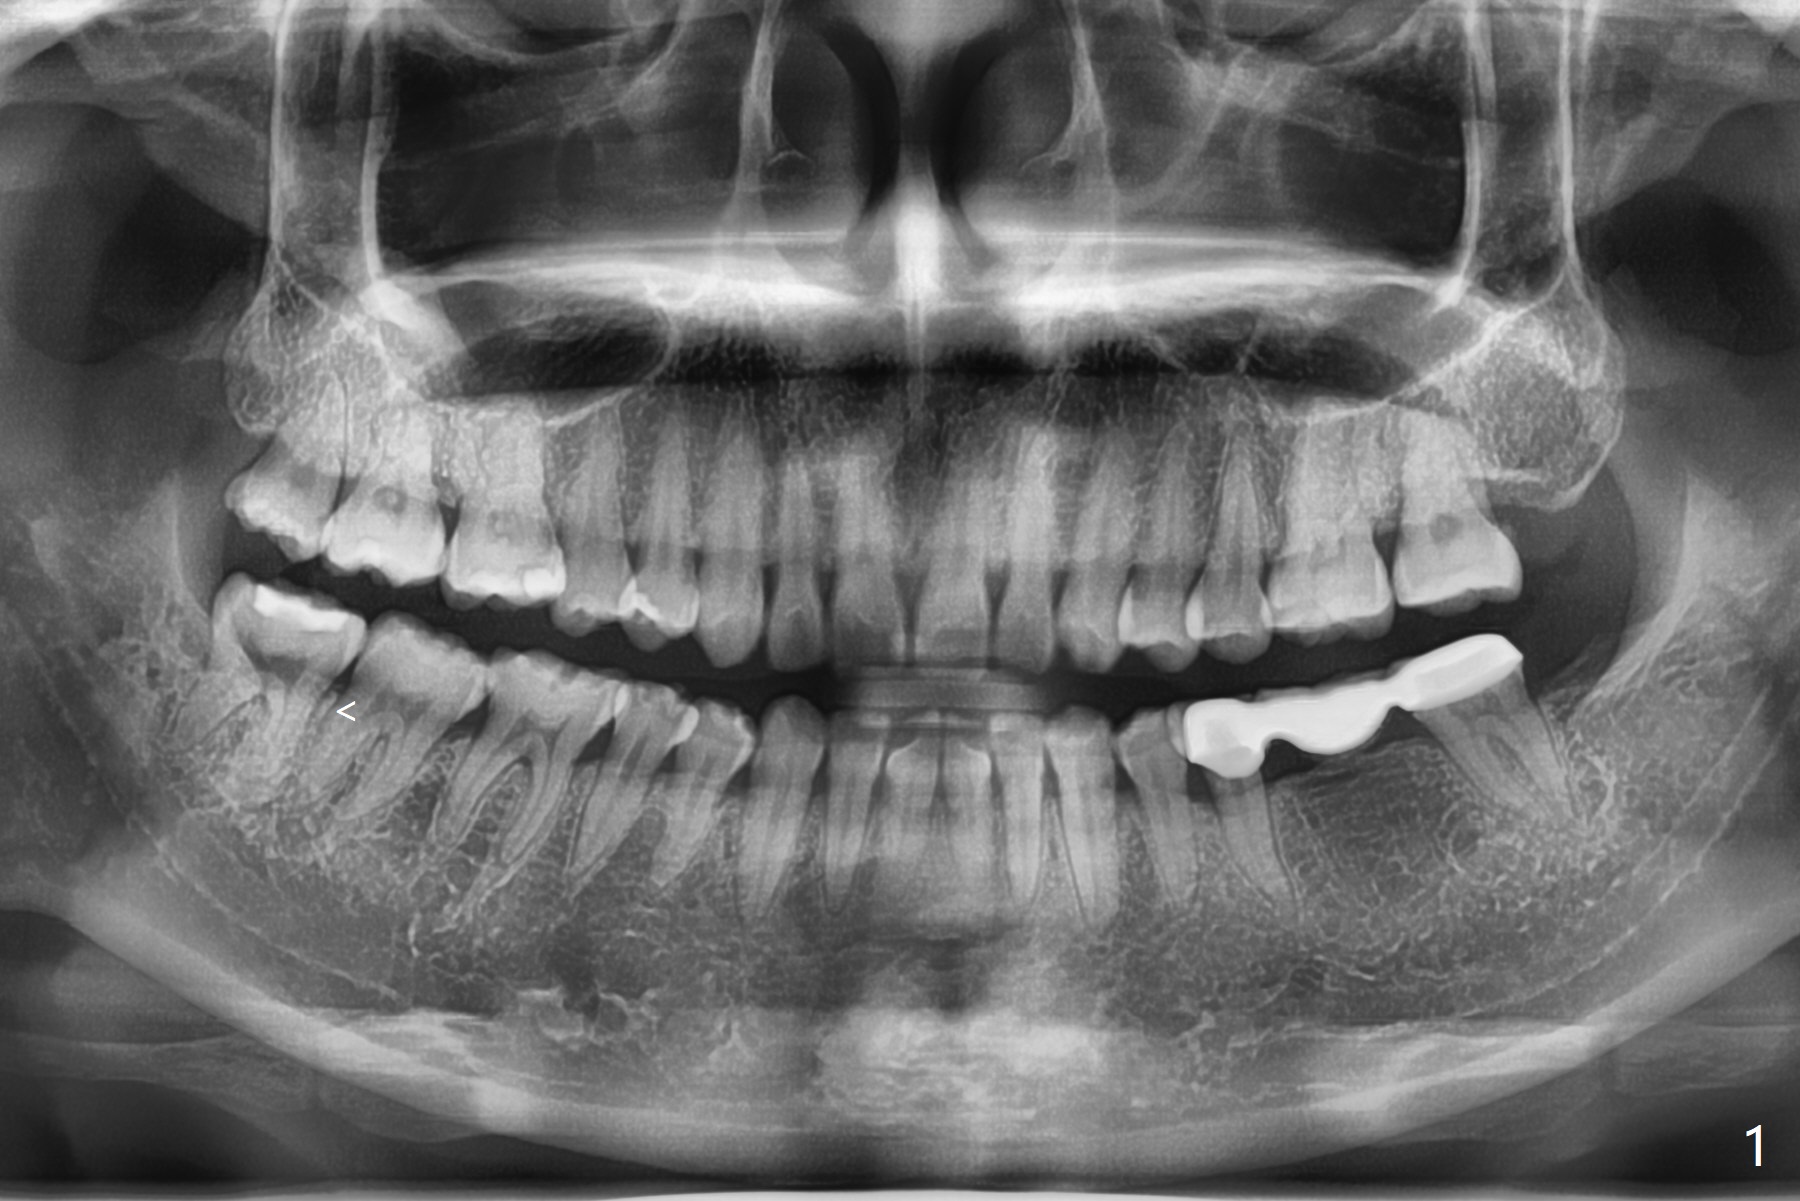

Thin Bone Between 2nd and 3rd Molars M

A 35-year-old woman has pericoronitis distal of #32. The bone between the 2nd and 3rd molars is high, but thin (Fig.1 <). With incision, buccal trough is created at #32 for elevators so that the 2nd molar is not affected by elevation. Collagen plug is placed in the socket to prevent dry socket (Fig.2). The mesial socket is completely ossified (Fig.3 *), while the distal one partially ossified 4 months postop. The ossification in the distal socket seems to be from coronal to apical (Fig.3 arrow), in contrast to the traditional thinking of apico-coronal.